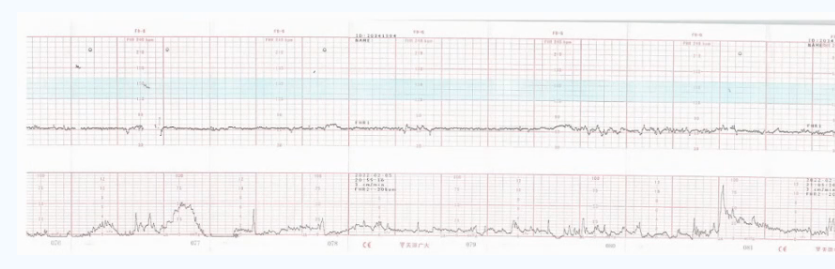

外监护属于无创性监护,目前临床常见的外监护设备大多基于超声多普勒技术探测胎心率,并结合宫腔压力探头探测宫腔压力或腹腔压力的变化,据此将胎心率、宫腔压力、母体心率共同描记构成胎心监护图形。

多普勒超声胎心监护

穿戴式胎心监护是基于电生理技术原理设计的外监护设备,弥补了多普勒探头和宫腔压力探头操作复杂、笨重和易受体位干扰的不足。通过贴附于孕妇腹部的穿戴式监测传感器,动态捕获母胎心电信号和子宫肌电信号,经计算机实时处理后描记形成胎心监护图形。这种技术可以避免胎儿心率和母体心率的混淆,有效解决胎心率断线、加倍、减半的问题,适合高危妊娠和胎心监护图形异常孕妇进行长时间连续监护[1]。

穿戴式胎心监护